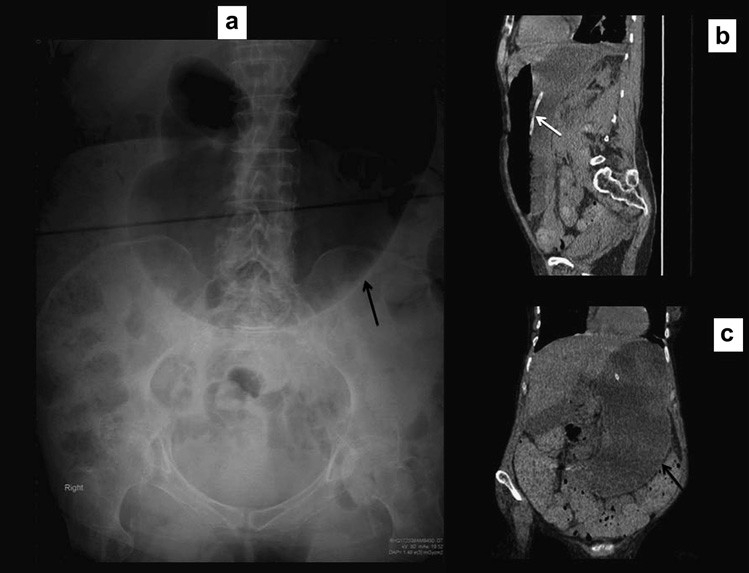

Nguyên nhân dẫn tới tắc ruột non, đặc biệt là thoát vị, đôi khi có thể nhận ra trên phim X quang và nên được tìm kiếm một các hệ thống trong tắc ruột. Điều này yêu cầu phim X quang bụng phải bao phủ cả vùng bẹn vì đó là vị trí hay thoát vị gây tắc ruột nhất. Thoát vị bịt hoặc thoát vị rốn đôi khi tạo nên các mẫu hình khí gợi ý trên phim X quang, do đó chụp cắt lớp vi tính kéo xuống mức thấp hơn để đánh giá chi tiết (Hình 2). Tắc ruột do sỏi mật và các khối ổ bụng gây tắc ruột đôi khi cũng có thể được phát hiện.

Hình 2. Tắc ruột non do thoát vị nghẹt lỗ bịt. (a) Nhiều quai ruột non giãn. Lưu ý có một ít khí dưới dây chằng bẹn ở lỗ bẹn phải (b,c) Chụp CT cho thấy một quai ruột ở giữa cơ bịt trong và cơ bịt ngoài, xác định thoát vị bịt bên phải gây tắc ruột.